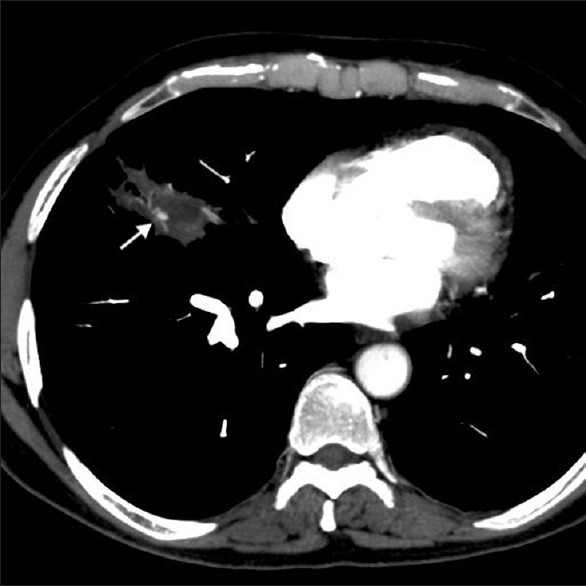

AIDS patient. Diagnosis?

Other imaging appearances?

Pneumocystis pneumonia. An opportunistic infection caused by Pneumocystis jiroveci. Most common in AIDS patients with profound T-cell immunosuppression, less commonly seen in patients with other forms of immunosuppression.

Imaging appearance: Ground-glass opacities in the parahilar regions and upper lobes. Severe cases may present with dense air-space consolidation. If there is interlobular septal thickening, can have crazy-paving pattern. May develop pulmonary cysts (risk of spontaneous pneumothorax). Chest x-ray can be normal. Pleural effusion and LAD uncommon.